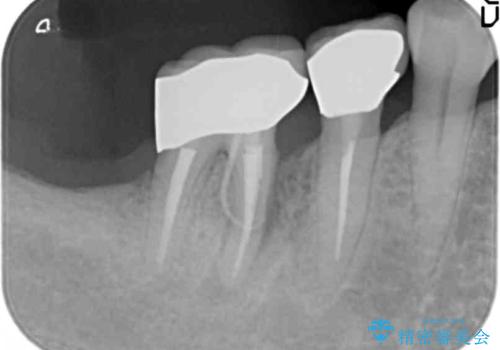

精査した結果、奥歯の根は破折しており抜歯を避けられない状況でした。

咬合力が強く、その他の歯の破折も防ぐために奥歯の咬合機能をインプラントを用いて回復する治療計画を立てます。

歯は大きな力がかかると割れてしまうことがよくあります。

破折した歯はほとんどの場合抜歯が必要になることが多く、インプラントを用いた咬合機能の回復は、また噛めるようになるだけでなく残っているその他の歯を守る意味でも非常に大きな意味を持ちます。